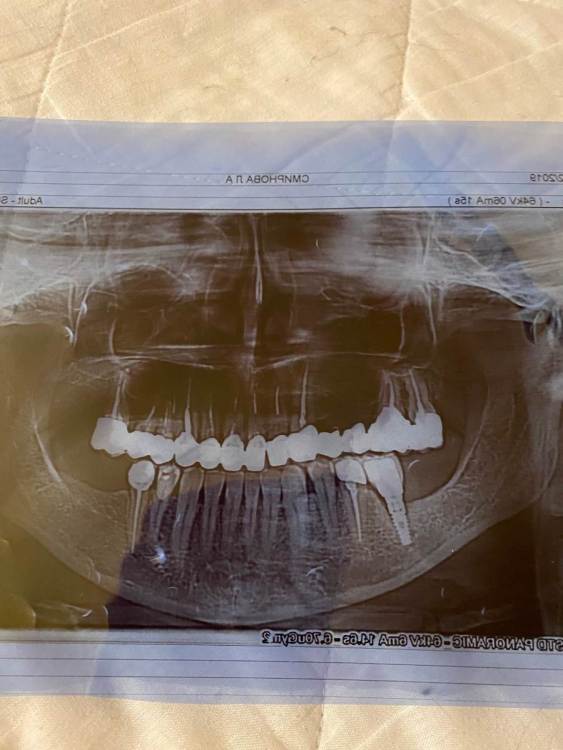

Smila Опубликовано 8 января, 2022 Поделиться Опубликовано 8 января, 2022 (изменено) Здравствуйте! Посоветуйте, пожалуйста, в моей ситуации с зубами что можно сделать.? На верхней челюсти стоят коронки( циркон). Протезирование было в 2016 году. С правовой стороны мостовидный протез, отсутствуют 4, 5,зубы,протез держится на клыке и соответственно на 6 и 7 зубах. В конце декабря 2019 года на клыке обнаружена киста, в острой фазе. Сделали Цистэктомию, через два месяца образовался свищь,, в июне 2020 повторная операция. Через полгода на контрольном КТ не образовалась надкостница, и меня беспокоили переодически боли, десна как бы горит. Врач подпилила мне коронки на нижней челюсти,сказала что видимо идёт постоянное напряжение на верхний клык и поэтому кость не нарастает. Консультировалась с несколькими врачами на кт ничего криминального не видели. И вот 2022 год воспаление сново. Возможно ли спасти зуб через перелечивание каналов? Или снести этот мост и удалить зуб, и сделать синуслифтиг? Мне предложили пролечить каналы через коронку, не снимая мост. Но я уже столько намучилась, хочется решить это основательно. Есть КТ от 4 января , не получается выложить, его прислали мне емайл. Изменено 8 января, 2022 пользователем Smila Ссылка на комментарий